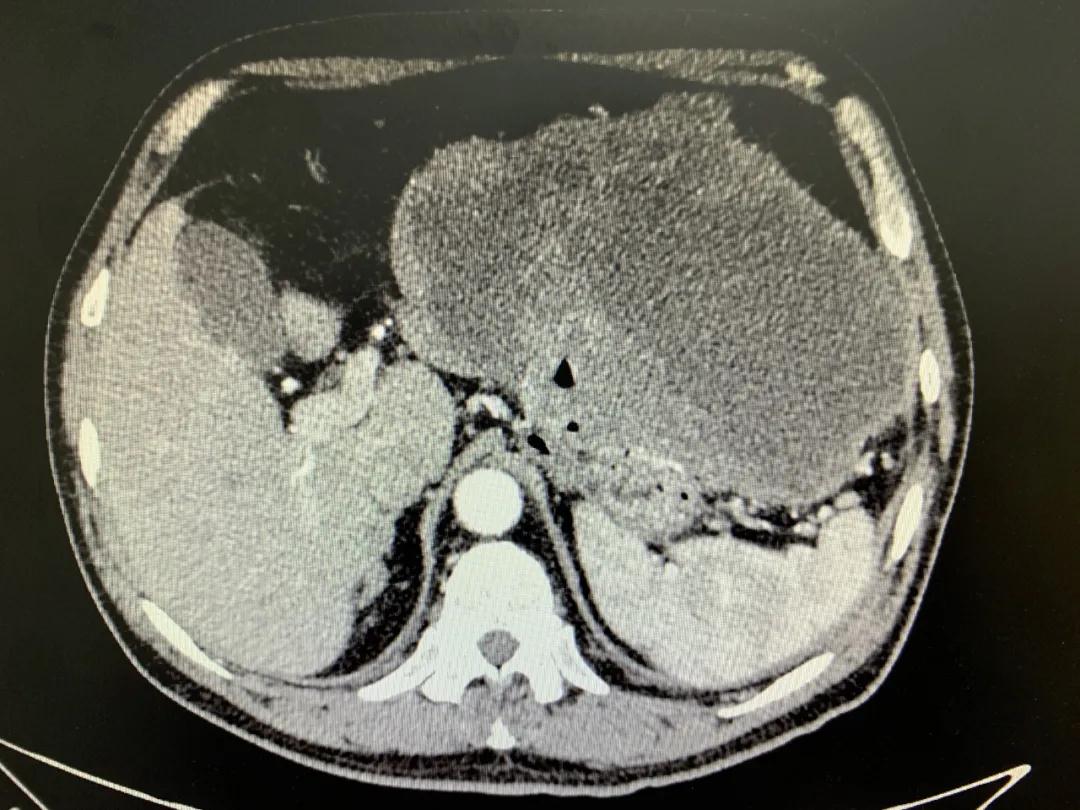

患者入院時(shí)血紅蛋白數(shù)值仍持續(xù)下降,出現(xiàn)失血性休克表現(xiàn),危及生命。消化外科二病區(qū)蔡磊主任接診后,組織科室迅速對(duì)患者進(jìn)行了全面的檢查。CT提示腫瘤大小約19.3*10.3cm,腫瘤內(nèi)提示大量積血。結(jié)合相關(guān)檢查,考慮為罕見的巨大胃間質(zhì)瘤合并出血。